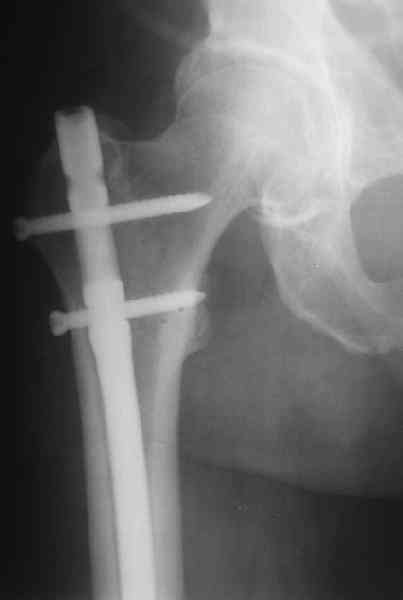

На операцию пошли, имея в возможных планах практически все прозвучавшие предложения - и про пластину, и про аппаратную коррекцию. Была даже несколько экстравагантная идея закрыто убрать винты из диафизарной части пластины, наложить аппарат, постепенно восстановить ось и длину, после чего вновь ввести винты в пластину, подложив шайбы между пластиной и костью.

А.Семенистый:

> Есть подозрение, что мыщелки отрепонированы между собой неидеально,

> как-будто наружный завален кзади (угол открыт кпереди). Надо удалять все

> железо, репонировать открыто суставные поверхности и...

Это предложение показалось слишком радикальным. Неровно оно совсем чуть, по межмыщелковой борозде, т.е. в ненагружемой зоне, да уже и срослось хотя бы там... И не 18 лет пациенту.

Удалили ластину без проблем. Выявилась значительная подвижность. В этих условиях сразу пропала мотивация к постепенной коррекции аппаратом. Попробовал восстановить длину, введя между отломками spreader. Отчасти удалось. Тогда защили рану, наложили спицевой дистрактор (2 спицы в дистальный отдел и 1 вверху). после этого был убран и спонгиозный винт. И сделали антгерадное штифтование, как говорится, "по принятой в

клинике методике".

С.Максимов:

> При остеосинтезе гвоздем кроме доступа для удаления пластины и

> репозиции необходим дополнительный доступ и дополнительная травма

> сустава (?).

Дополнительные доступы для введения гвоздя и проксимальных винтов понадобились, но они маленькие, по 1 см. Нижние винты ввели прямо между швами. Суставы дополнительно не травмировали, и даже ввели гвоздь не через f. piriformis, а через большой вертел.

Длину восстановили, возможно, даже с изьбытком, ну да динамизируем пораньше. Введенные в овальное отверстие дистальые винты имеют угловую стабильность. Снимки приложены. Заранее спасибо за критику и комментарии.